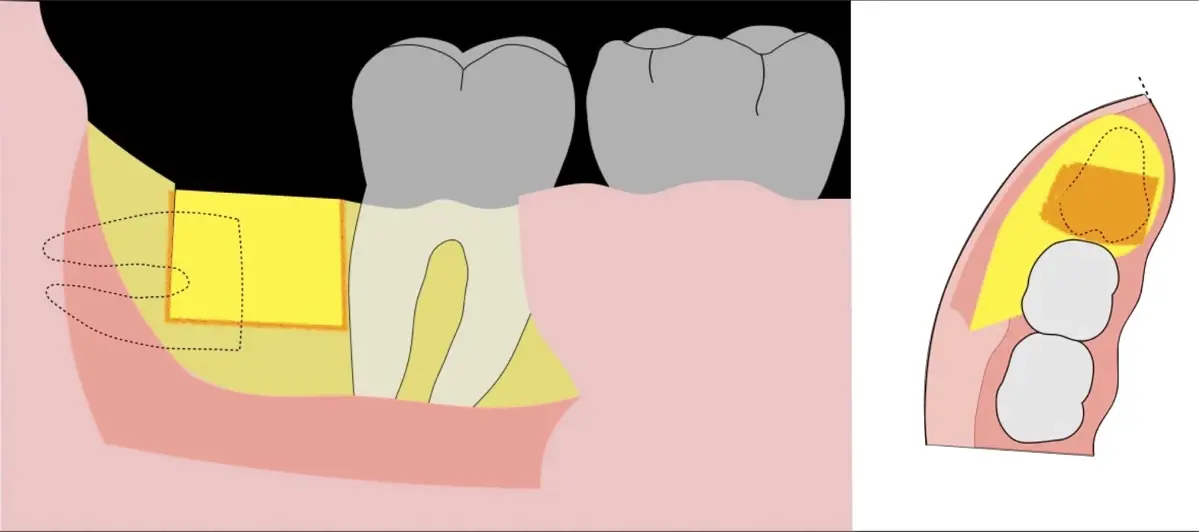

Figura 4. Demarcación de la zona de osteotomía con insertos de corte recto y/o angulado a nivel oclusal. Vista frontal (a). Vista oclusal (b).

Figura 5. Fractura y eliminación oclusal del fragmento óseo de la porción coronal oclusal.